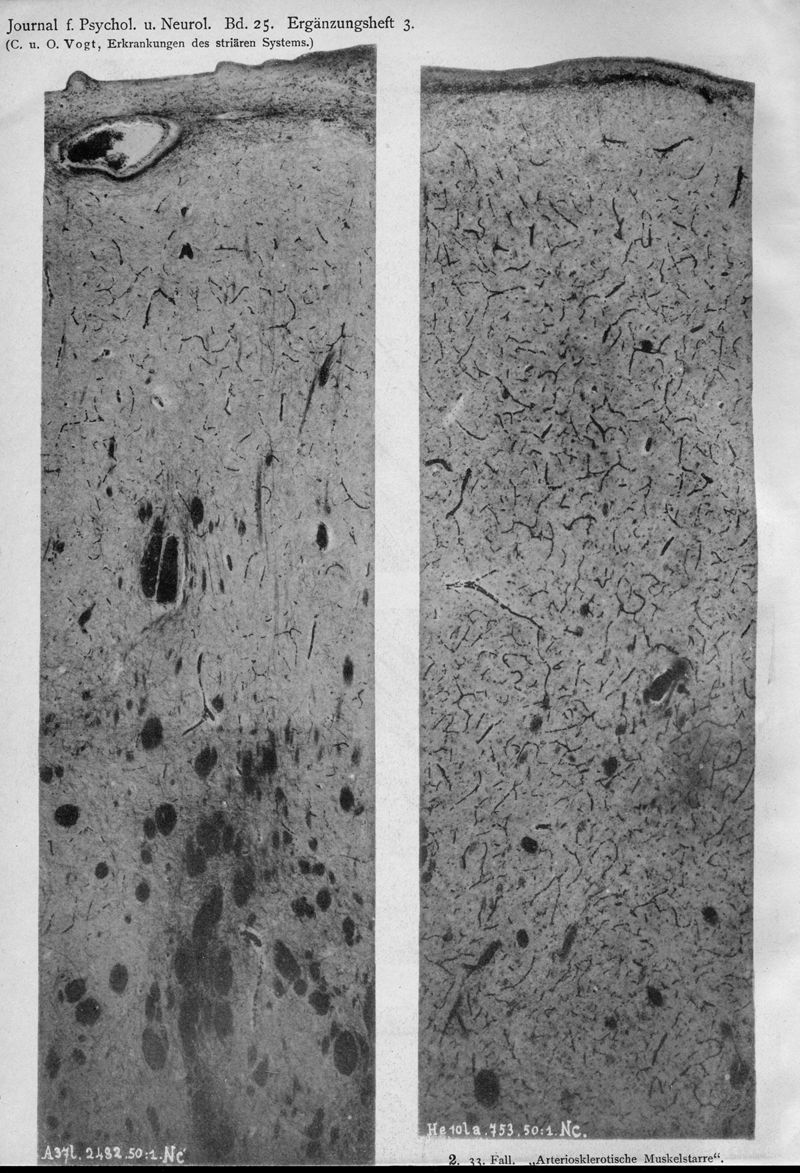

VOGT, Cécile / VOGT, O.

In : Journal für Psychologie und Neurologie,

1920, Vol. 25, pp. 627-846